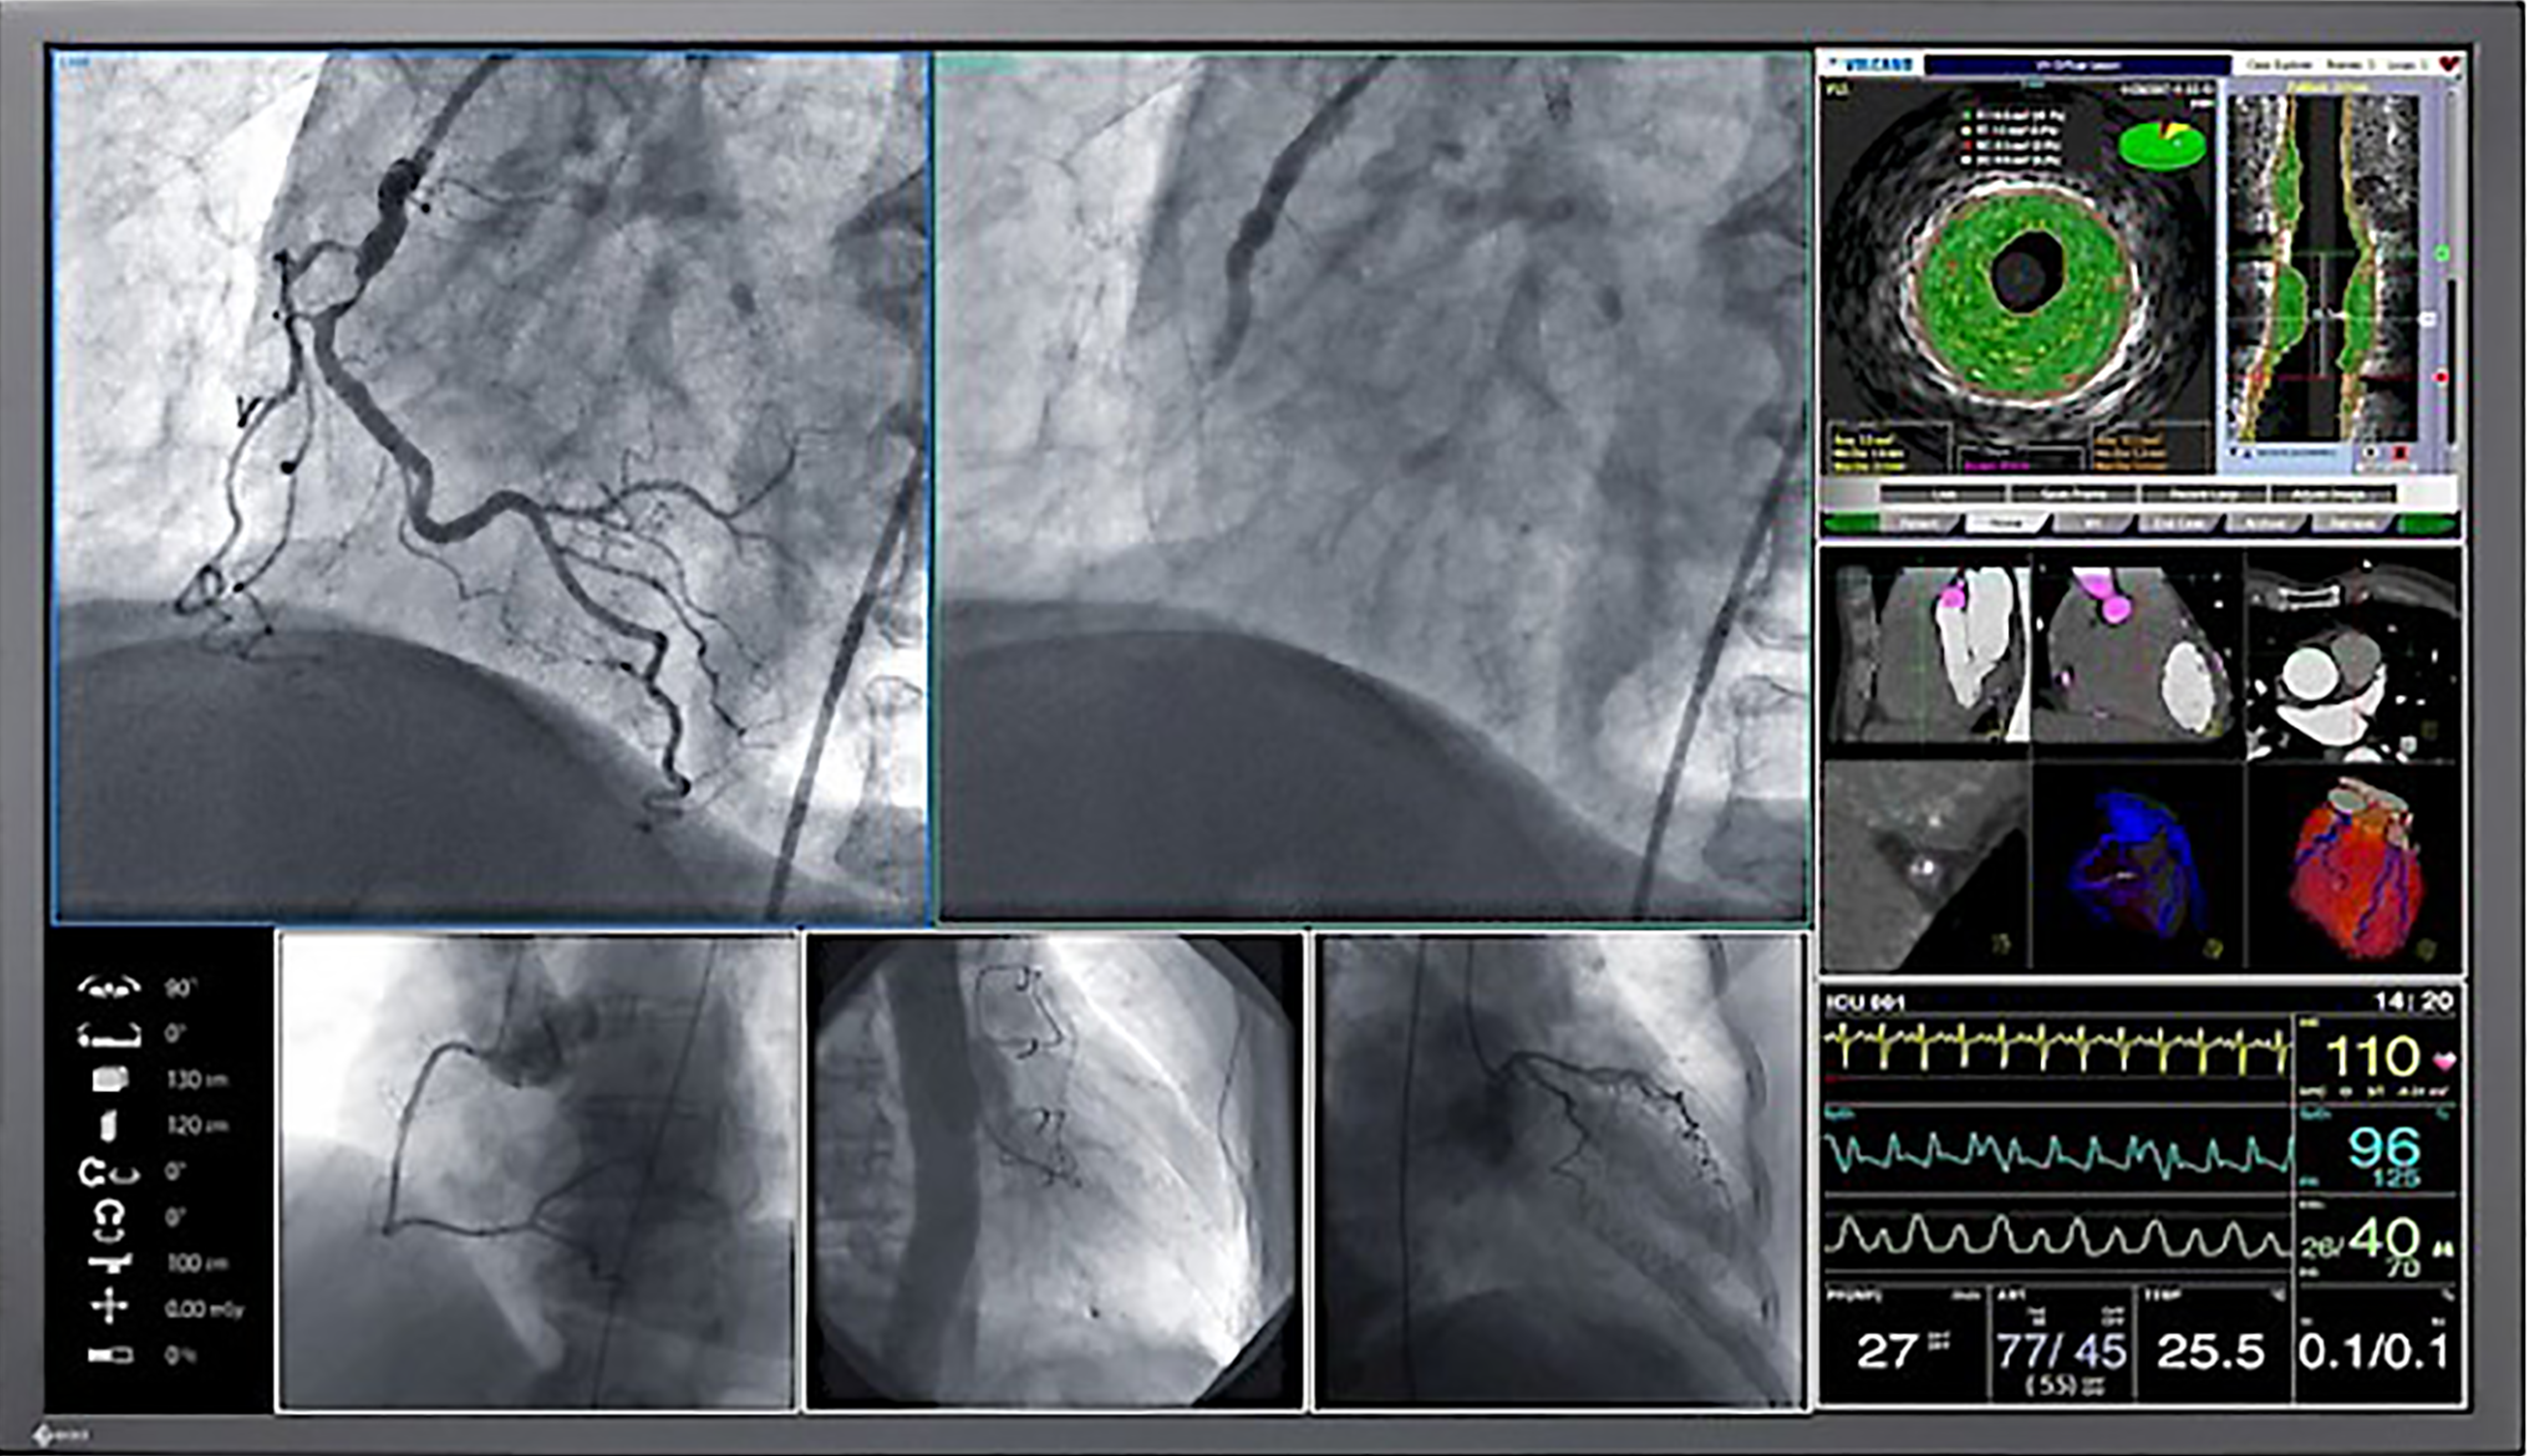

As the variety of different picture sources increases, state-of-the-art operating rooms are increasingly shifting from traditional X-ray film to displaying images on monitors. These images range from boom and endoscopy cameras to C-arms and Picture Archiving and Communication Systems (PACS). With EIZO’s surgical monitors, all images can be conveniently provided for clear decision-making and the highest diagnostic precision.